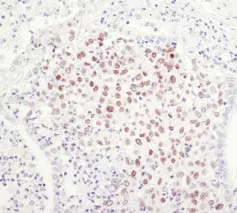

免疫组织化学法(Immunohistochemistry, IHC):是一种使用抗体检测和分析蛋白质表达,同时保持天然组织的组成、细胞特征和结构的技术。IHC 常用于确认肿瘤或其他组织癌变的形态特征。 请注意:以上步骤是石蜡包埋样品的制备流程。 IHC 是一项具有挑战性的应用技术,应用过程中常出现各种问题。在此,本文将讨论我们所认为的成功实验的关键步骤,并提供关于试剂以及实验过程的建议。旨在通过提供建议来帮助您改进IHC 检测,减少您的实验优化过程,快速达到预期结果。 抗原修复 --解开“封印”的钥匙 石蜡包埋样品,因为固定时形成的化学交联可通过阻止抗体与抗原接触来防止抗体结合;因此,需通过称为抗原修复(也称为抗原暴露或抗原表位修复)的过程来解交联。抗原修复可通过热诱导的方法(heat–induced epitope retrieval, HIER)或者通过酶解法实现。 在抗体验证过程中,Cell Signaling Technology(CST)为每个一抗确定了最佳流程,并将此信息纳入产品数据表。SignalStain® Citrate Unmasking Solution (10X) #14746 和 SignalStain® EDTA Unmasking Solution (10X) #14747 是 CST 针对抗原修复提供的两种选择。 抗原修复缓冲液选择 适用于HIER 的缓冲液有多种。而CST 常推荐的两种缓冲液是:pH6, 10mM 柠檬酸盐缓冲液和pH 8, 1mM EDTA 缓冲液。缓冲液是否适用于您的实验取决于您所使用的一抗。请查阅产品说明书中所推荐的用于特异性抗体的修复缓冲液。一般而言,EDTA 缓冲液适用于多数磷酸化酪氨酸特异性抗体,而柠檬酸盐缓冲液适用于其他多数抗体。 如下图所示,适当的修复缓冲液对最终染色质量具有显著影响。 使用CST推荐的修复缓冲液可改善最终染色结果。 在利用柠檬酸盐缓冲液(左)或者EDTA缓冲液(右)对抗原进行修复后,利用Phospho–HER3/ErbB3 (Tyr1289) (D1B5) Rabbit mAb #2842 对石蜡包埋人类肺部肿瘤进行IHC分析。如图所示,利用EDTA缓冲液进行抗原修复可使细胞膜染色度增强的同时可加强信号。请查阅产品说明书中与抗体适配的修复缓冲液。 煮沸装置 载玻片在所推荐的缓冲液中加热煮沸一段时间后,才可引起抗原修复。我们建议使用微波炉或高压锅加热煮沸以达到最佳抗原修复效果。 一抗使用和抗体稀释 --特异性的灵魂 一抗选择至关重要 一抗在检测中至关重要,对数据质量存在直接影响。要选择经多重严格验证过的IHC抗体。来自 CST 的所有 IHC 验证抗体不仅已确认在组织中具有强信号,而且经过严格的验证程序来确认信号的特异性。在 CST 专门从事 IHC 的科学家们检测了大量的抗体,并只推荐了最适合该应用的抗体。 另外,需要留意抗体可检测的样本类型,通常IHC-P 是指石蜡组织切片的免疫组化,IHC-F 指的是冰冻组织切片的免疫组化。 一抗稀释液 抗体稀释剂可显著影响信号强度。在IHC–P中,SignalStain®Antibody Diluent #8112 在用作推荐抗体的稀释剂时可提供更好的染色。 也有多种抗体稀释液可供选择,在CST,我们利用 SignalStain®抗体稀释液、TBST/5% NGS(含5%山羊血清的 TBST)或者 PBST/5% NGS(含5%山羊血清的 PBST)来稀释一抗。因为合适的稀释剂具有抗体特异性,因此,查阅产品说明书中针对使用的抗体所推荐的稀释剂。在进行 IHC–F过程中,一抗应在封闭缓冲液(TBS/0.3% Triton™ X–100/5% NGS)中稀释。 为获得最佳实验结果,如产品说明书所述,始终使用推荐的一抗稀释液。 使用SignalStain®抗体稀释液(左)或TBST/5%NGS(右)作为抗体稀释液,利用Phospho–Akt (Ser473) (D9E) XP® Rabbit mAb #4060 或Phospho–EGF Receptor (Tyr1173) (53A5) Rabbit mAb #4407对石蜡包埋人类乳腺肿瘤(上图)和HCC827异种移植物(下图)进行IHC分析。如图所示,与 #4060 在TBST/5% NGS中稀释后所得信号强度相比,经SignalStain® 抗体稀释液稀释所得信号强度更强。相比之下,#4407在TBST/5%NGS中稀释后的效果更好。请查阅产品说明书中针对所选特异性抗体的推荐稀释液。 检测系统 --信号放大的引擎 传统的 IHC 检测方法利用了亲和素和生物素间的天然亲和性。这种亲和素–生物素–复合物 (ABC) 系统需要进行两步法检测:包括结合生物素化二抗后暴露于亲和素–HRP 复合物,然后进行显色反应。基于生物素的系统容易导致背景染色,特别是含有大量内源性生物素的肝脏、肾脏等组织。 因此,我们建议使用基于聚合物的检测系统,如SignalStain® Boost IHC 检测试剂。该基于聚合物的检测系统不含生物素,而包含了直接偶联于聚合物主链上的酶和二抗。SignalStain® Boost IHC 检测试剂具有高敏感性并消除因内源性生物素所致的假阳性染色,其检测过程省去一个步骤为检测过程节省了时间,并且其与所有基于过氧化物酶的底物相容。 左:基于生物素的检测; 右:基于聚合物的检测 相对于基于生物素的检测而言,基于聚合物的检测的敏感性更高。 利用Sox2 (D6D9) XP® Rabbit mAb #3579 对石蜡包埋的人类肺部肿瘤进行IHC分析,采用基于生物素的检测(左)或基于聚合物的检测(SignalStain® Boost IHC Detection Reagent #8114;(右)。如图所示,基于聚合物的检测敏感度更高,染色强度更好。 SignalStain® Boost IHC Detection Reagent (HRP, Mouse) #8125 和 SignalStain® Boost IHC Detection reagent (HRP, Rabbit) #8114可分别在 IHC 检测中用于检测小鼠或兔一抗。 色原显色 --结果的“定格” 二氨基联苯胺 (DAB) 底物是基于过氧化物酶检测系统中最常用的色原之一。DAB 与HRP 反应以在抗体结合处形成棕色沉淀物。 并非所有 DAB 底物均可达到同等的效果。在实验中建议始终使用高质量的DAB 底物。在CST公司,IHC 小组的CST科学家内部鉴定IHC抗体所使用的都是SignalStain® DAB 底物试剂盒#8059。 SignalStain® DAB 底物试剂盒敏感性高,且与一抗的作用效果最佳。 并非所有 DAB 底物均可达到同等的效果。利用 Phospho-Stat3 (Tyr705) (D3A7) XP® Rabbit mAb #9145 对石蜡包埋的人乳腺癌进行的 IHC 分析。使用SignalStain® DAB Substrate Kit #8059(左图)或另一家公司提供的 DAB(右图)进行显色法检测。SignalStain® DAB Substrate Kit 产生的信号比另一家公司提供的 DAB 更强。 使用与一抗匹配的优化试剂和操作流程能够大大改善您的实验结果。 抗体只是实验成功的因素之一。选择帮助抗体展现最好表现的配套产品同样重要。CST 提供的配套产品与CST科学家用于验证IHC一抗的试剂相同。为与CST的一抗和实验步骤配套使用,这些产品已经过全面优化,所以您完全可以相信您的结果。 部分IHC 配套试剂/试剂盒